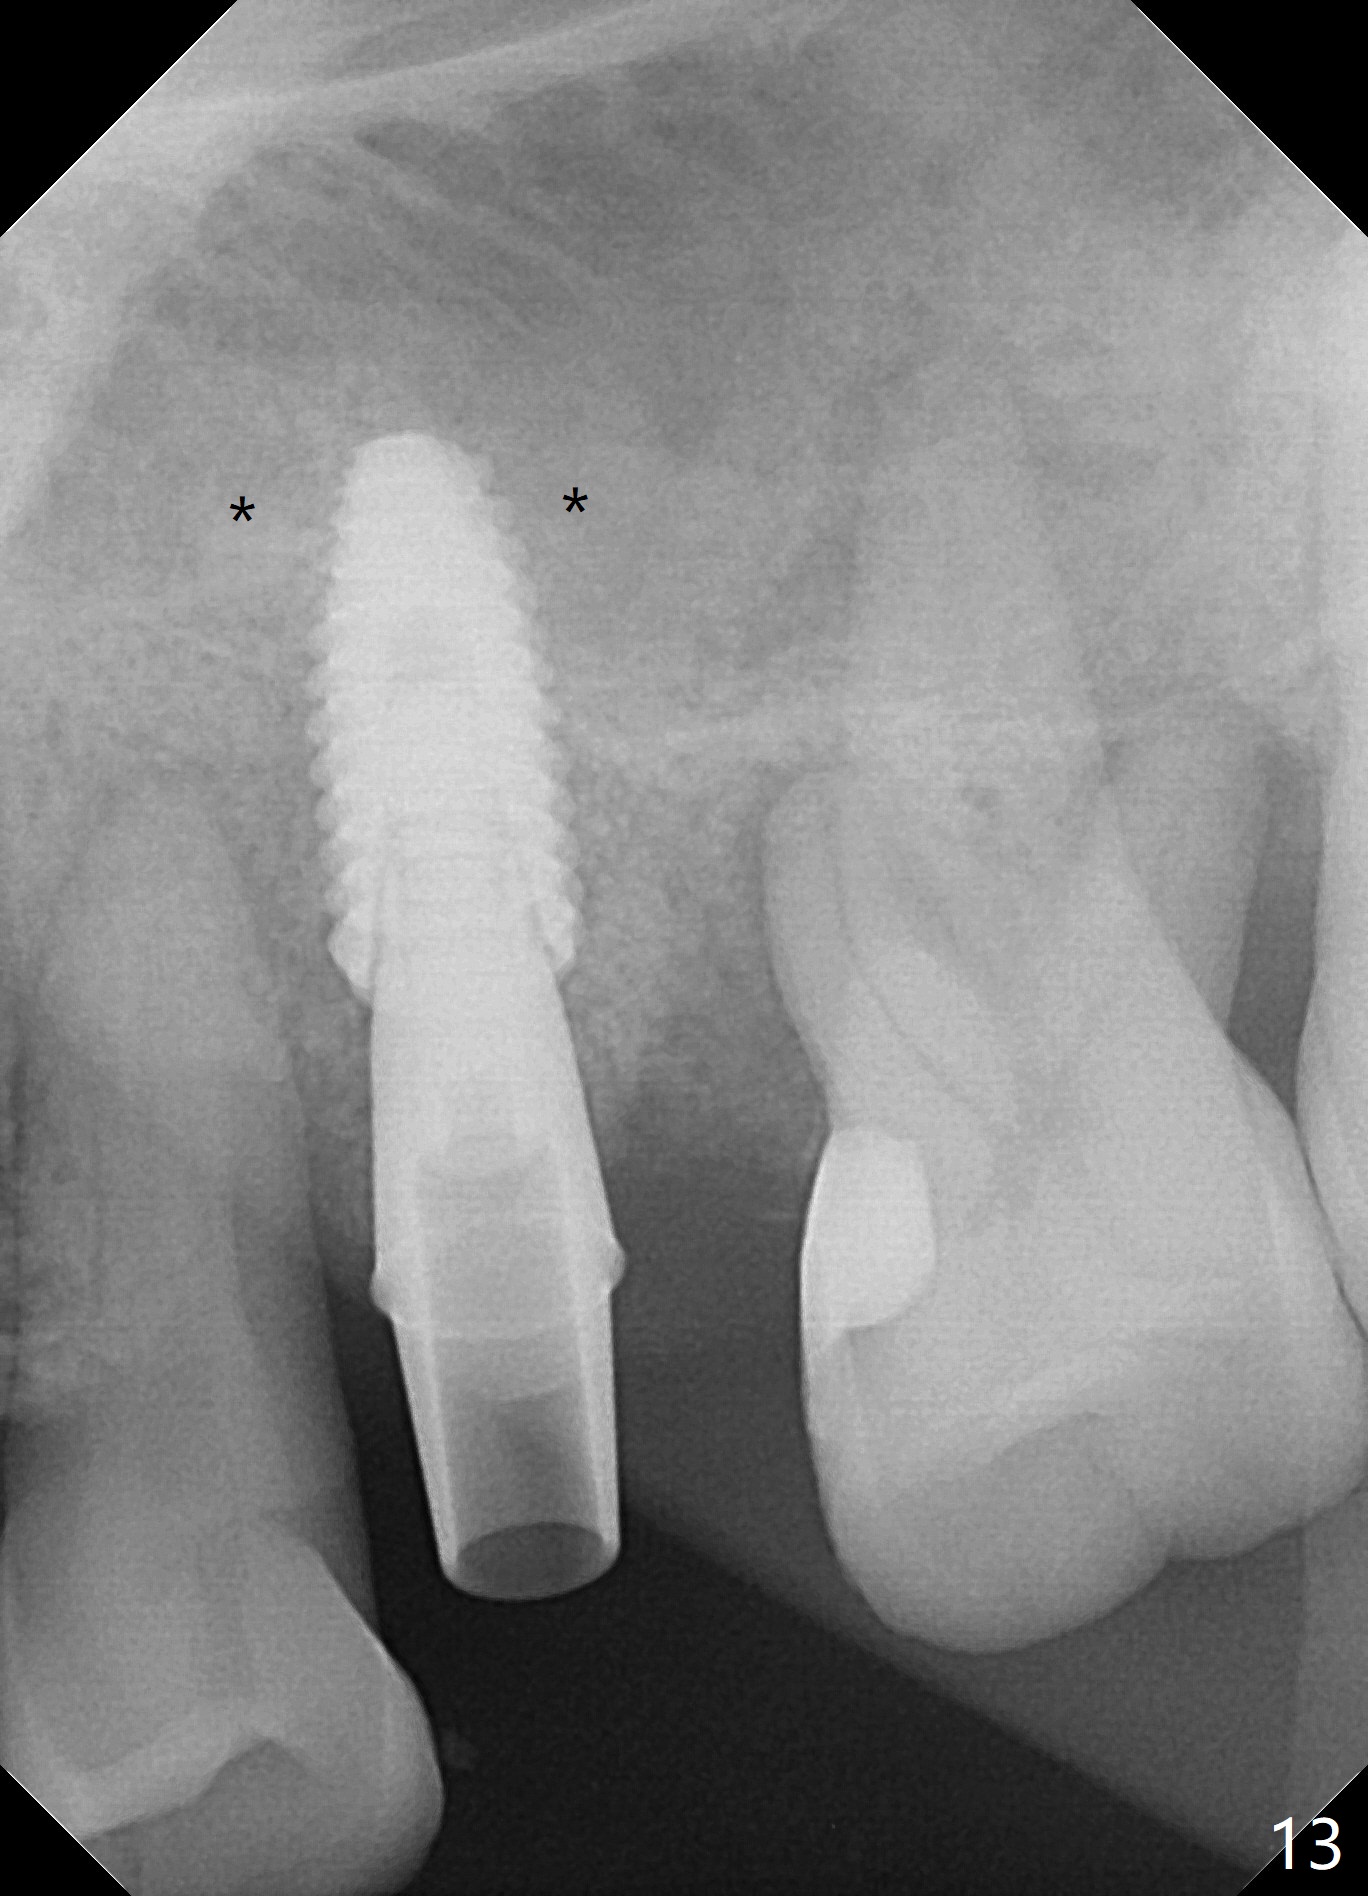

There is more bone apical to the residual root at #13 (Fig.1 red line). An immediate implant along the long axis of the root can be longer, 11.5 mm, favorable for primary stability (Fig.2 (CT taken immediately preop)). The initial trajectory is not ideal (Fig.3). When the pointed/Lindamann bur is removed (Fig.4), effort is made to move the apical end of the osteotomy distal (Fig.5 red arrow) by removing the apical bone (red dashed line). Following sequential osteotomy, a 4x10 mm dummy implant is placed with the trajectory remaining not so ideal (Fig.6,7). As the dummy implant is removed (Fig.8), a new osteotomy is established distal to the existing one (Fig.9). Subsequent drills gradually shift into the original osteotomy (Fig.10 red arrow). When the same dimension dummy implant returns, the trajectory improves with decreased stability (Fig.11). It seems reasonable to place a larger implant without further osteotomy. After placing PRF membrane and Vanilla graft for sinus lift (Fig.13 *), a 4.5x10 mm definitive implant is placed with loss of control in the trajectory (Fig.12,13).

When the initial osteotomy is off substantially (Fig.4), an osteotomy should be established de novo and as early as possible (Fig.14) so that subsequent osteotomy will not relapse to a great extent. More ideally, the initial osteotomy should be planned correctly (Fig.15,16) with sacrifice of the bone height. Nearly 1 month postop, the 4.5x5.5(5) cementation abutment is loose. When it is removed, the patient feels pain from the implant. A 5.5x6 mm healing abutment is placed instead. The implant osteointegrates with trabecular pattern in the sinus 9 months postop (Fig.20 *). The gingiva around the crown at #13 is healthy 1 year 4 months post cementation (Fig.18). Check the distal surface of #13 for bone loss if the tooth #14 is to be extracted.